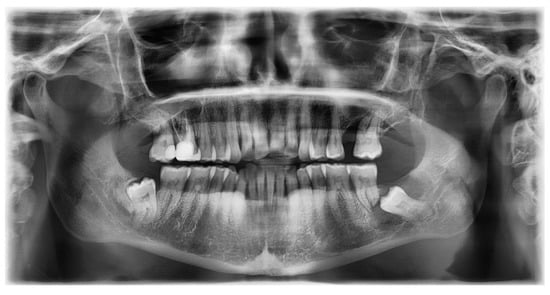

On an OPG X-ray, teeth #38 and 48 were impacted and distally orientated (Figure 10). Tooth #38 showed a radiotransparent lesion measuring 20 × 15 mm, with a well-defined border, multilocular appearance, and a thin septum, most compatible with a DC versus ameloblastoma versus odontogenic keratocyst.

On CBCT X-ray, the distal root of the impacted tooth #38 was in contact with the upper wall of the left IAC, generating a discreet deformation of the canal (Figure 11). The cyst showing a multilocular aspect was located adjacent to the crown of tooth #38 and seemed to be attached to the tooth neck. The lesion extending slightly to the ascending branch of the mandible measured 17 mm in height, 21 mm in length and 10 mm in width. In its caudal part, the lesion was in contact with the upper wall of the IAC over about 13 mm. The wall was thinned but with little impact on its internal diameter. The vestibular and lingual cortex were also strongly thinned focally. There was no periosteal reaction or fracture at the mandibular angle. On the bases of these radiological findings, the differential diagnosis included DC, ameloblastoma, and odontogenic keratocyst.